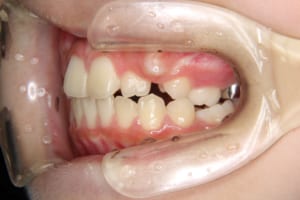

治療前

| 年齢・性別 | 11才 女性 |

| 主訴 | 八重歯の生え方が気になる |

| その他/備考 | 上の犬歯が生えるためのスペースが全くない状態でした。放置すると重度の八重歯になることが想定されるケースです。 今回はあごの成長も利用しながら治療をするために、早めに後期治療(大人の矯正治療)に移行しました。 治療後レントゲン写真を見たところ、上顎前歯に若干の歯根吸収を認めました。 |